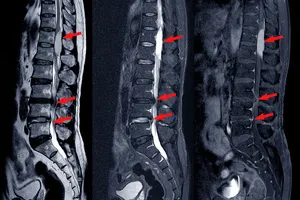

척추관협착증은 척추뼈 안쪽 통로인 척추관이 좁아져 신경을 압박하여 허리 통증, 다리 저림, 감각 이상 등의 증상을 유발하는 질환입니다. 이러한 증상이 심하거나 보존적인 치료(약물 치료, 물리치료 등)에도 불구하고 호전되지 않을 경우 수술적 치료를 고려하게 됩니다.

수술의 목적은 좁아진 척추관을 넓혀 신경을 압박하는 요인을 제거하고, 이로 인해 발생하는 통증과 신경 증상을 완화시키는 것입니다.